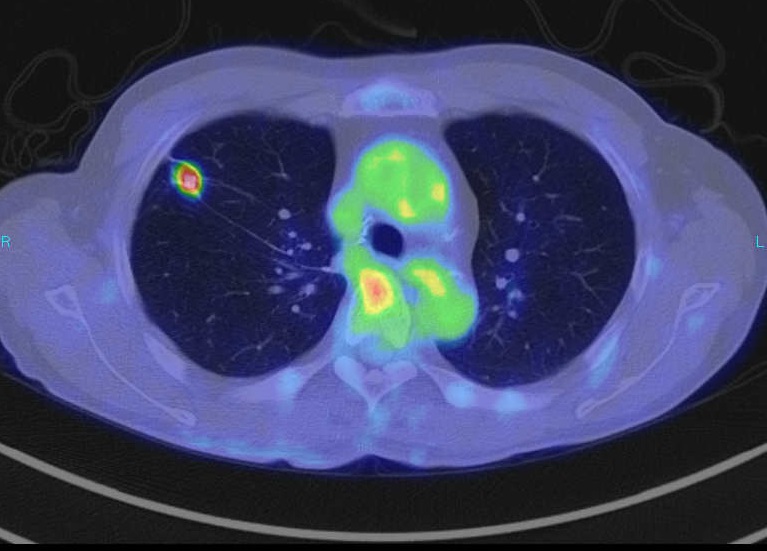

PET-CT検査画像(右肺がん)